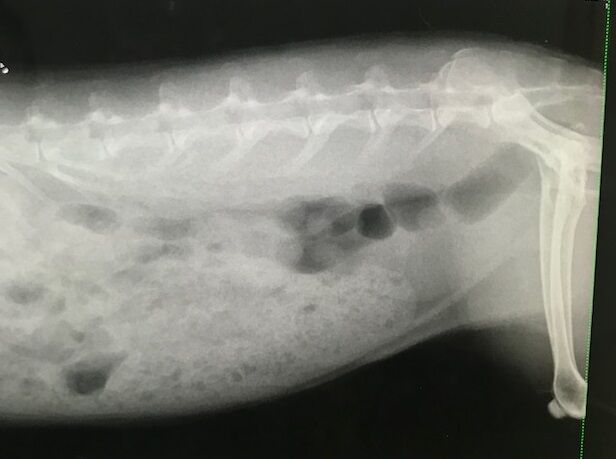

で、お歳、なこともあるのか呼吸の様子も少し気になってたので、

念のためのレントゲンをお願いしました。

胸、お腹、諸々特に問題視する箇所はありませんでした